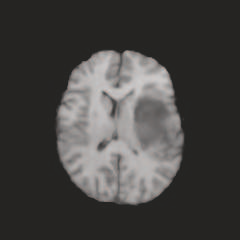

Multi-modal medical image completion has been extensively applied to alleviate the missing modality issue in a wealth of multi-modal diagnostic tasks. However, for most existing synthesis methods, their inferences of missing modalities can collapse into a deterministic mapping from the available ones, ignoring the uncertainties inherent in the cross-modal relationships. Here, we propose the Unified Multi-Modal Conditional Score-based Generative Model (UMM-CSGM) to take advantage of Score-based Generative Model (SGM) in modeling and stochastically sampling a target probability distribution, and further extend SGM to cross-modal conditional synthesis for various missing-modality configurations in a unified framework. Specifically, UMM-CSGM employs a novel multi-in multi-out Conditional Score Network (mm-CSN) to learn a comprehensive set of cross-modal conditional distributions via conditional diffusion and reverse generation in the complete modality space. In this way, the generation process can be accurately conditioned by all available information, and can fit all possible configurations of missing modalities in a single network. Experiments on BraTS19 dataset show that the UMM-CSGM can more reliably synthesize the heterogeneous enhancement and irregular area in tumor-induced lesions for any missing modalities.